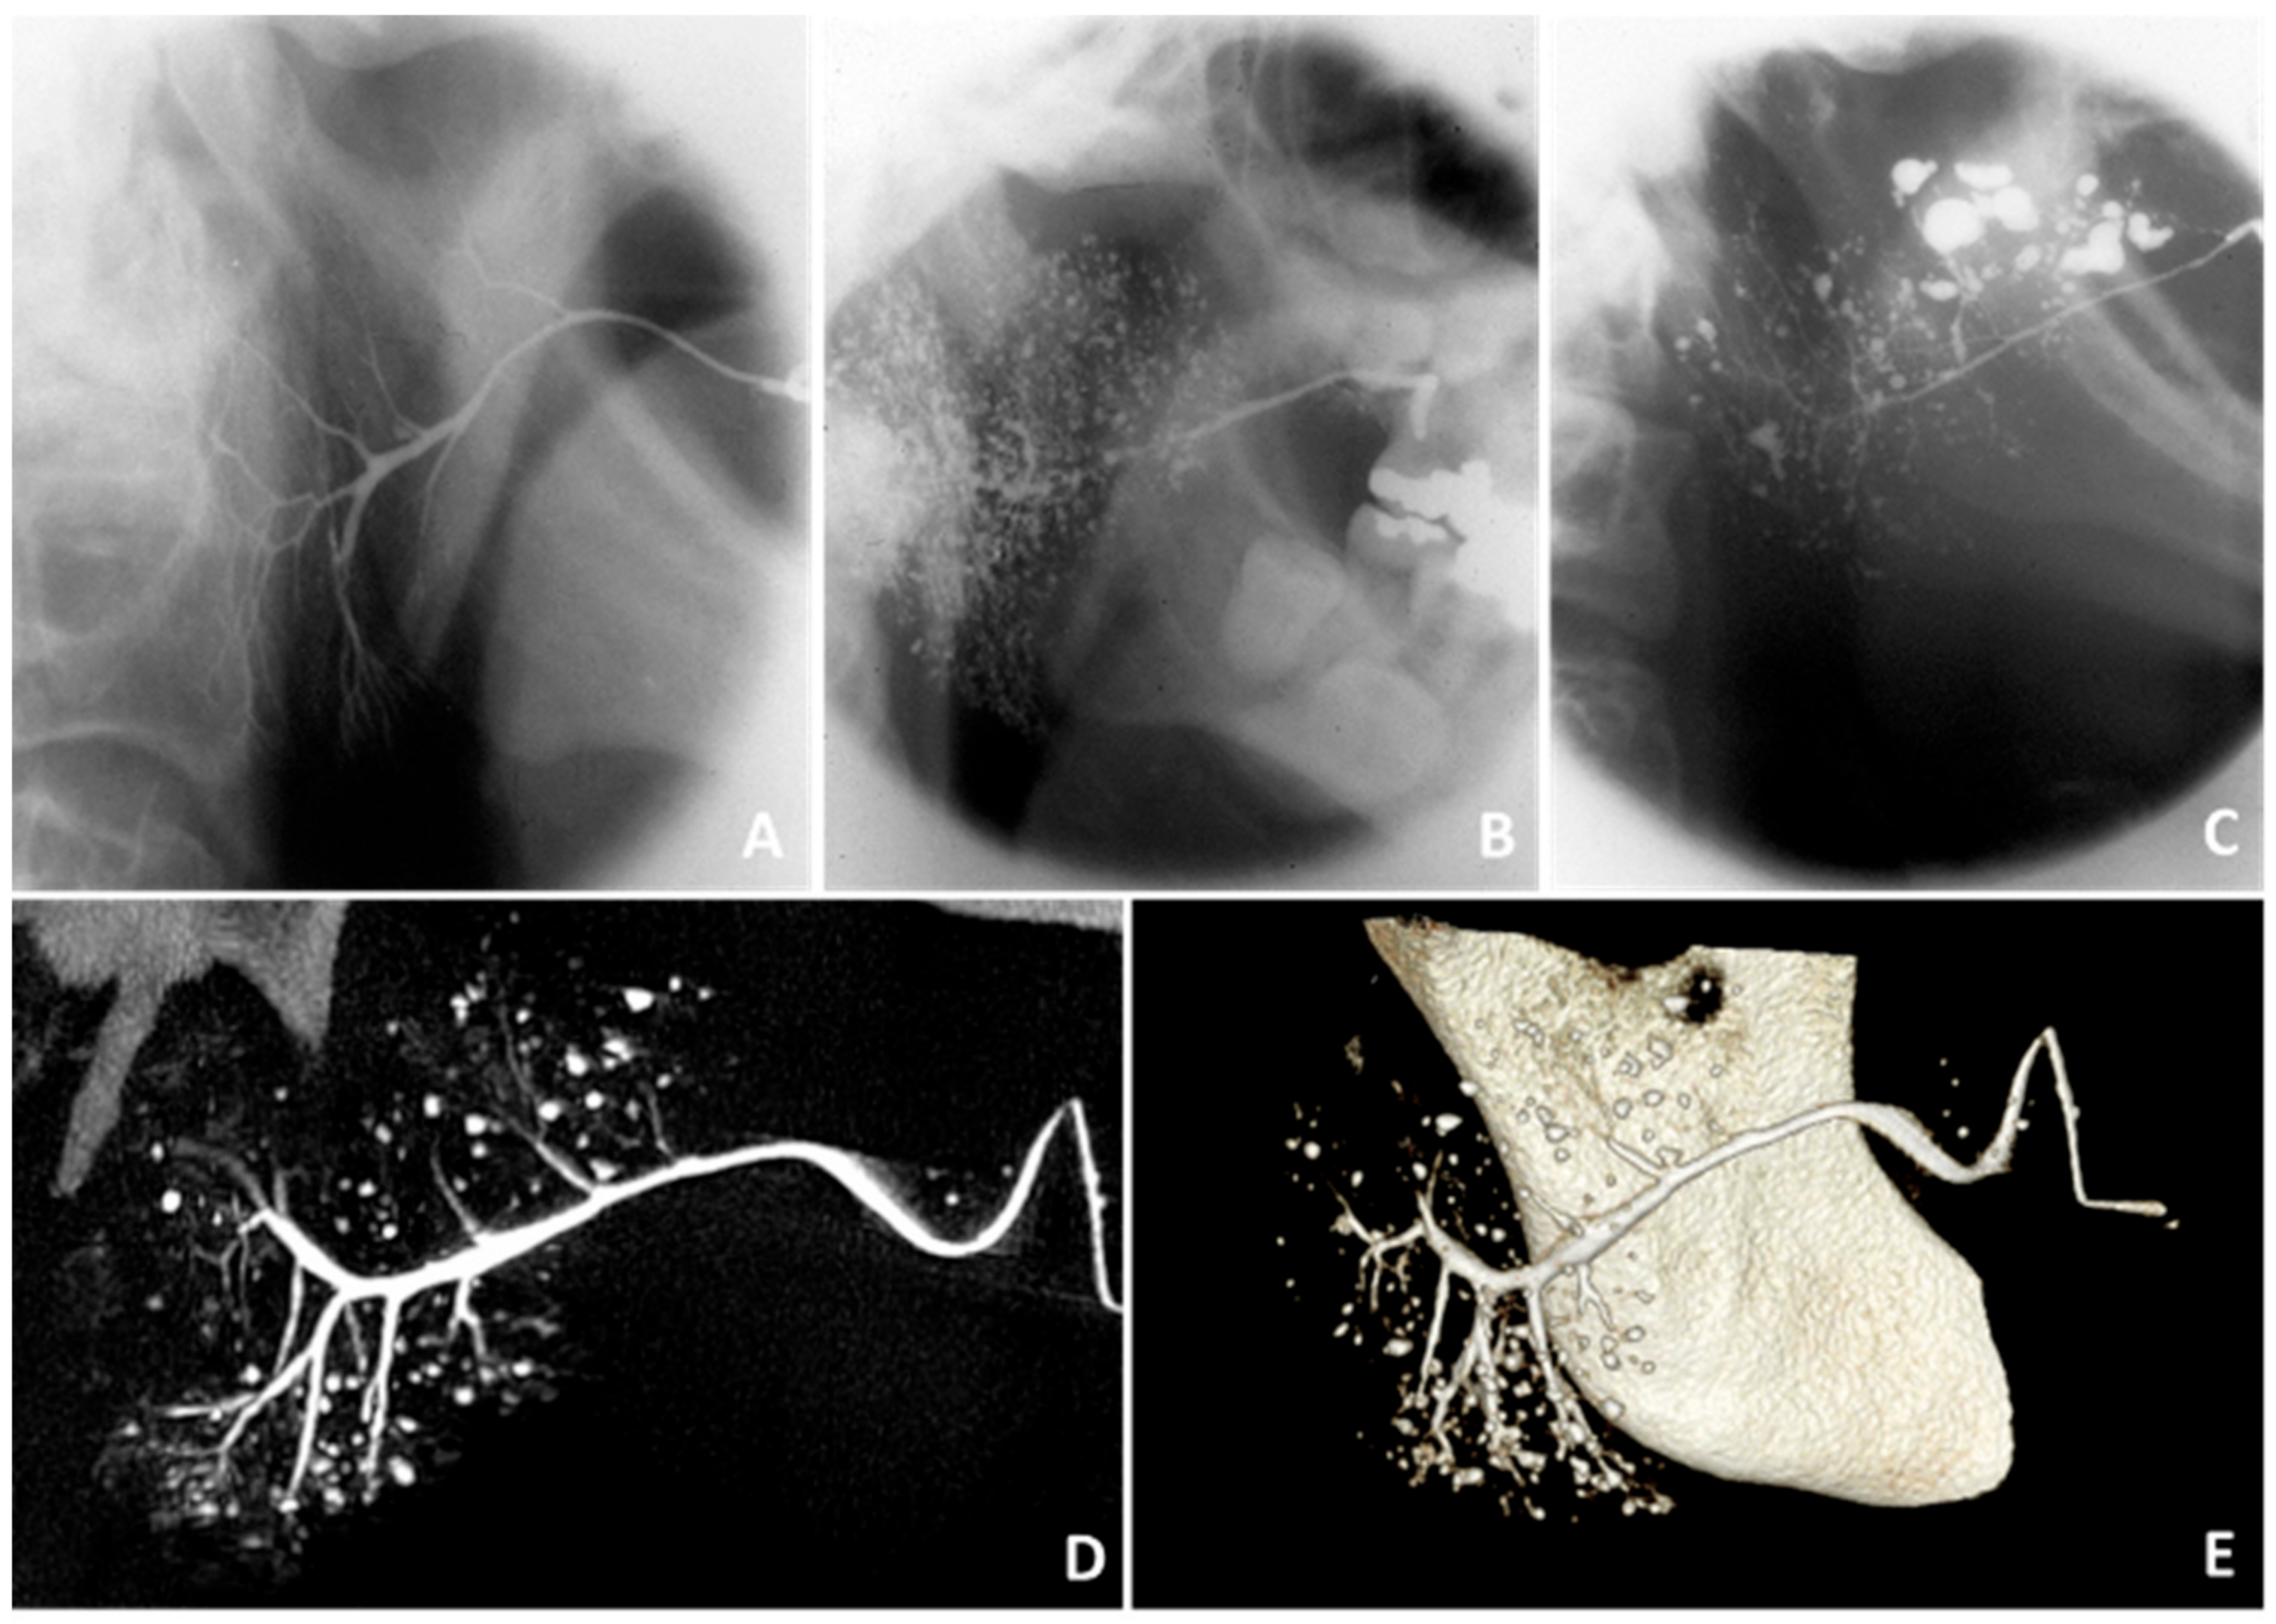

- Rubin, P.; Holt, J. Secretory sialography in diseases of the major salivary glands. Am. J. Roentgenol. Radium Ther. Nucl. Med. 1957, 77, 575–598. [Google Scholar]

- Swiecka, M.; Maślińska, M.; Paluch, L.; Zakrzewski, J.; Kwiatkowska, B. Imaging methods in primary Sjögren’s syndrome as potential tools of disease diagnostics and monitoring. Reumatologia 2019, 57, 336–342. [Google Scholar] [CrossRef] [PubMed][Green Version]

- Golder, W.; Stiller, M. Verteilungsmuster des Sjögren-Syndroms: Eine sialographische Studie. Z. Rheumatol. 2014, 73, 928–933. [Google Scholar] [CrossRef] [PubMed]

- Keshet, N.; Aricha, A.; Friedlander-Barenboim, S.; Aframian, D.J.; Nadler, C. Novel parotid sialo-cone-beam computerized tomography features in patients with suspected Sjogren’s syndrome. Oral Dis. 2019, 25, 126–132. [Google Scholar] [CrossRef] [PubMed]

| Sialography | + | + | − | − | -Moderate to High Sensitivity and Specificity | -Invasive -Contrast Medium |